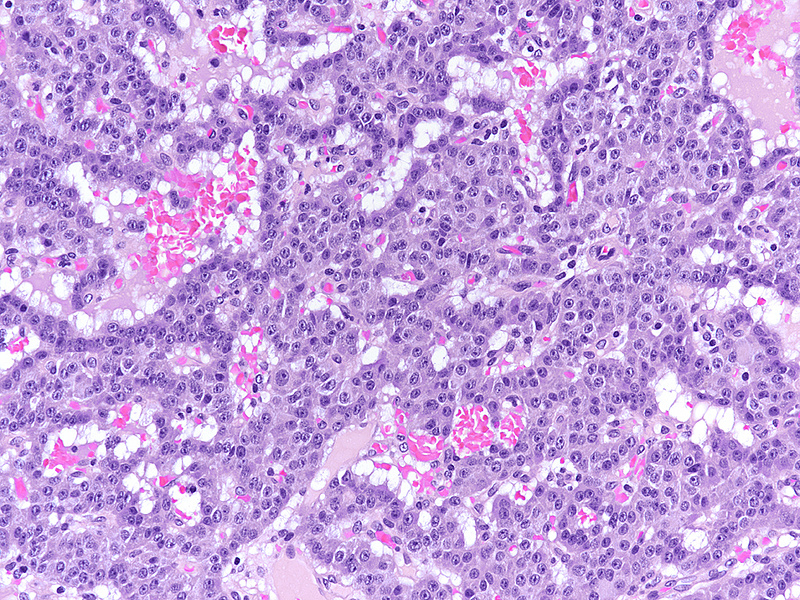

Upon magnetic resonance imaging (MRI) the pancreas contains several cystic lesions plus one partly solid, partly cystic lesion with a maximum diameter of 15 mm within the body. This lesion shows a biphasic pattern (Panel A). There are cysts lined by mucin-producing columnar cells with low grade dysplasia, consistent with a diagnosis of intraductal papillary mucinous neoplasm (IPMN). Other parts show a mainly solid, but also pseudoglandular growth of cuboidal cells with eosinophilic granular cytoplasm and centrally placed nuclei with “salt and pepper” chromatin and small nucleoli (Panels B-C). Mitoses are not detected. The two components merge with each other (Panel D), and in some foci the eosinophil granular cells underline the columnar cells (Panel E). The solid tumour component is strongly positive for synaptophysin (Panel F) and chromogranin A (Panel G), as are the underlining cells within the cystic component (Panel H). The Ki67 proliferation rate is low in the columnar epithelium (Panel I) and even lower (4%) in the solid component (Panel J). It is of note that the cells within the solid component express glucagon, while the cyst-lining mucus-producing cells are negative (Panels K-L).